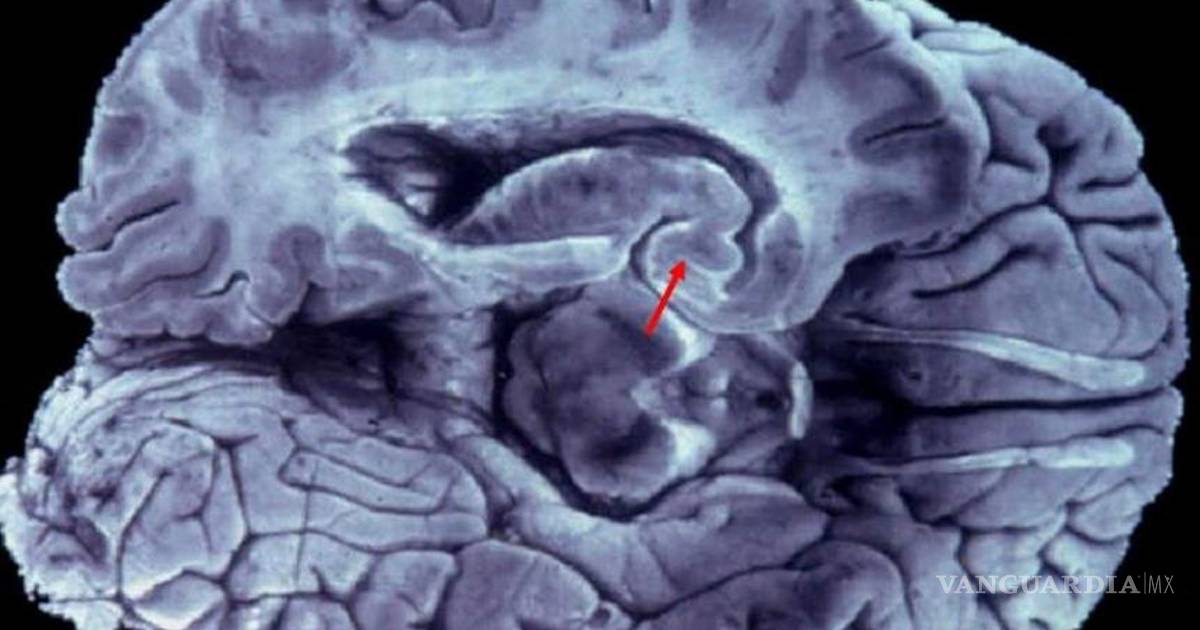

Esta enfermedad degenerativa, descrita hace más de un siglo por Alois Alzheimer, afecta entre el 3 y el 4% de la población y a partir de los 65 años.

Madrid, España.- La aparición de la enfermedad de Alzheimer es sutil. Comienza con trastornos de la memoria reciente, dificultad para encontrar palabras de uso habitual en el lenguaje, perdida de interés en las actividades diarias, olvidos frecuentes, reiteración al preguntar cosas. En ocasiones son los familiares o las personas de su entorno las primeras que aprecian estos problemas, y es muy frecuente que el paciente incluso niegue estos inicios de la enfermedad.

A pesar de los esfuerzos en investigación, a día de hoy, los complejos mecanismos por los que se desencadena la enfermedad de Alzheimer son aún una gran incógnita para la comunidad científica, por lo que seguimos sin contar con un tratamiento curativo. Sin embargo, contamos con un amplio arsenal de tratamientos que ayudan a ralentizar el proceso de degeneración neuronal que se produce durante la enfermedad. Pero para aplicarlos de forma eficaz es fundamental diagnosticar la enfermedad en su fase más temprana.

Junto con el tratamiento farmacológico para intentar enlentecer el progreso de la enfermedad, se ha demostrado que es muy recomendable la estimulación cognitiva y física de los pacientes en centros especializados. La rehabilitación cognitiva busca reforzar las funciones mentales afectadas por la enfermedad, tratando de aumentar la reserva neuronal, así como el número de conexiones entre células cerebrales y la densidad de sus redes.